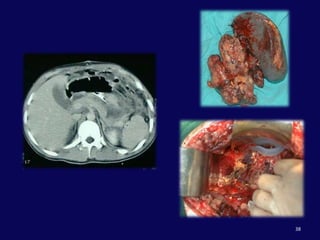

KANALIN KESİLDİĞİ DİSTAL YARALANMALARDistal pankreatektomiSplenektomiRoux-en-Y anastomozuMultitravmalı hastalarda zaman açısından uygun değildir.

Pankreas travması: PankreatikoduodenektomiendikasyonlarıPankreas başından ve/veya yandaş damarsal yapılardan  masif, kontrol edilemeyen kanamaPankreas başında masif ve rekonstrükte edilemeyecek duktal yaralanmaRekonstrükte edilemeyecek kombine yaralanmalar:Duodenum ve pankreas başıDuodenum, pankreas başı ve koledok

HepatoduodenalligamanPankreasDuodenum 2. kıta

PortalvenSMV

Portal venKoledokSplenik venDudenumSMVPankreas başı